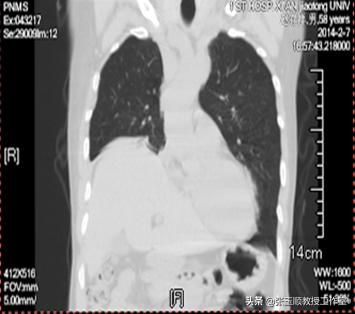

王先生既往无高血压、糖尿病、房颤病史,吸烟史30年,平均20支/日,已戒烟2年。入院后查体:血压正常,言语欠流利,左侧鼻唇沟稍浅,伸舌稍偏左。右下肺叩诊浊音、呼吸音减弱,心律齐,心音有力。腹部未发现异常。入院后除血气分析发现氧分压很低(46mmHg),二氧化碳分压正常(40mmHg),余血液各项检查均正常。医生给予无创呼吸机辅助通气,抗感染、平喘化痰等治疗,但治疗效果不佳。为查明病因,医院先后做了多项检查,胸部CT:右肺中叶肺不张、右肺下叶炎症、右肺上叶肺大泡、右肺下叶钙化灶、右侧膈肌抬高、纵隔淋巴结钙化;头颅CT:多发腔隙性脑梗死。

图1 胸部CT:右侧膈肌抬高、纵隔淋巴结钙化